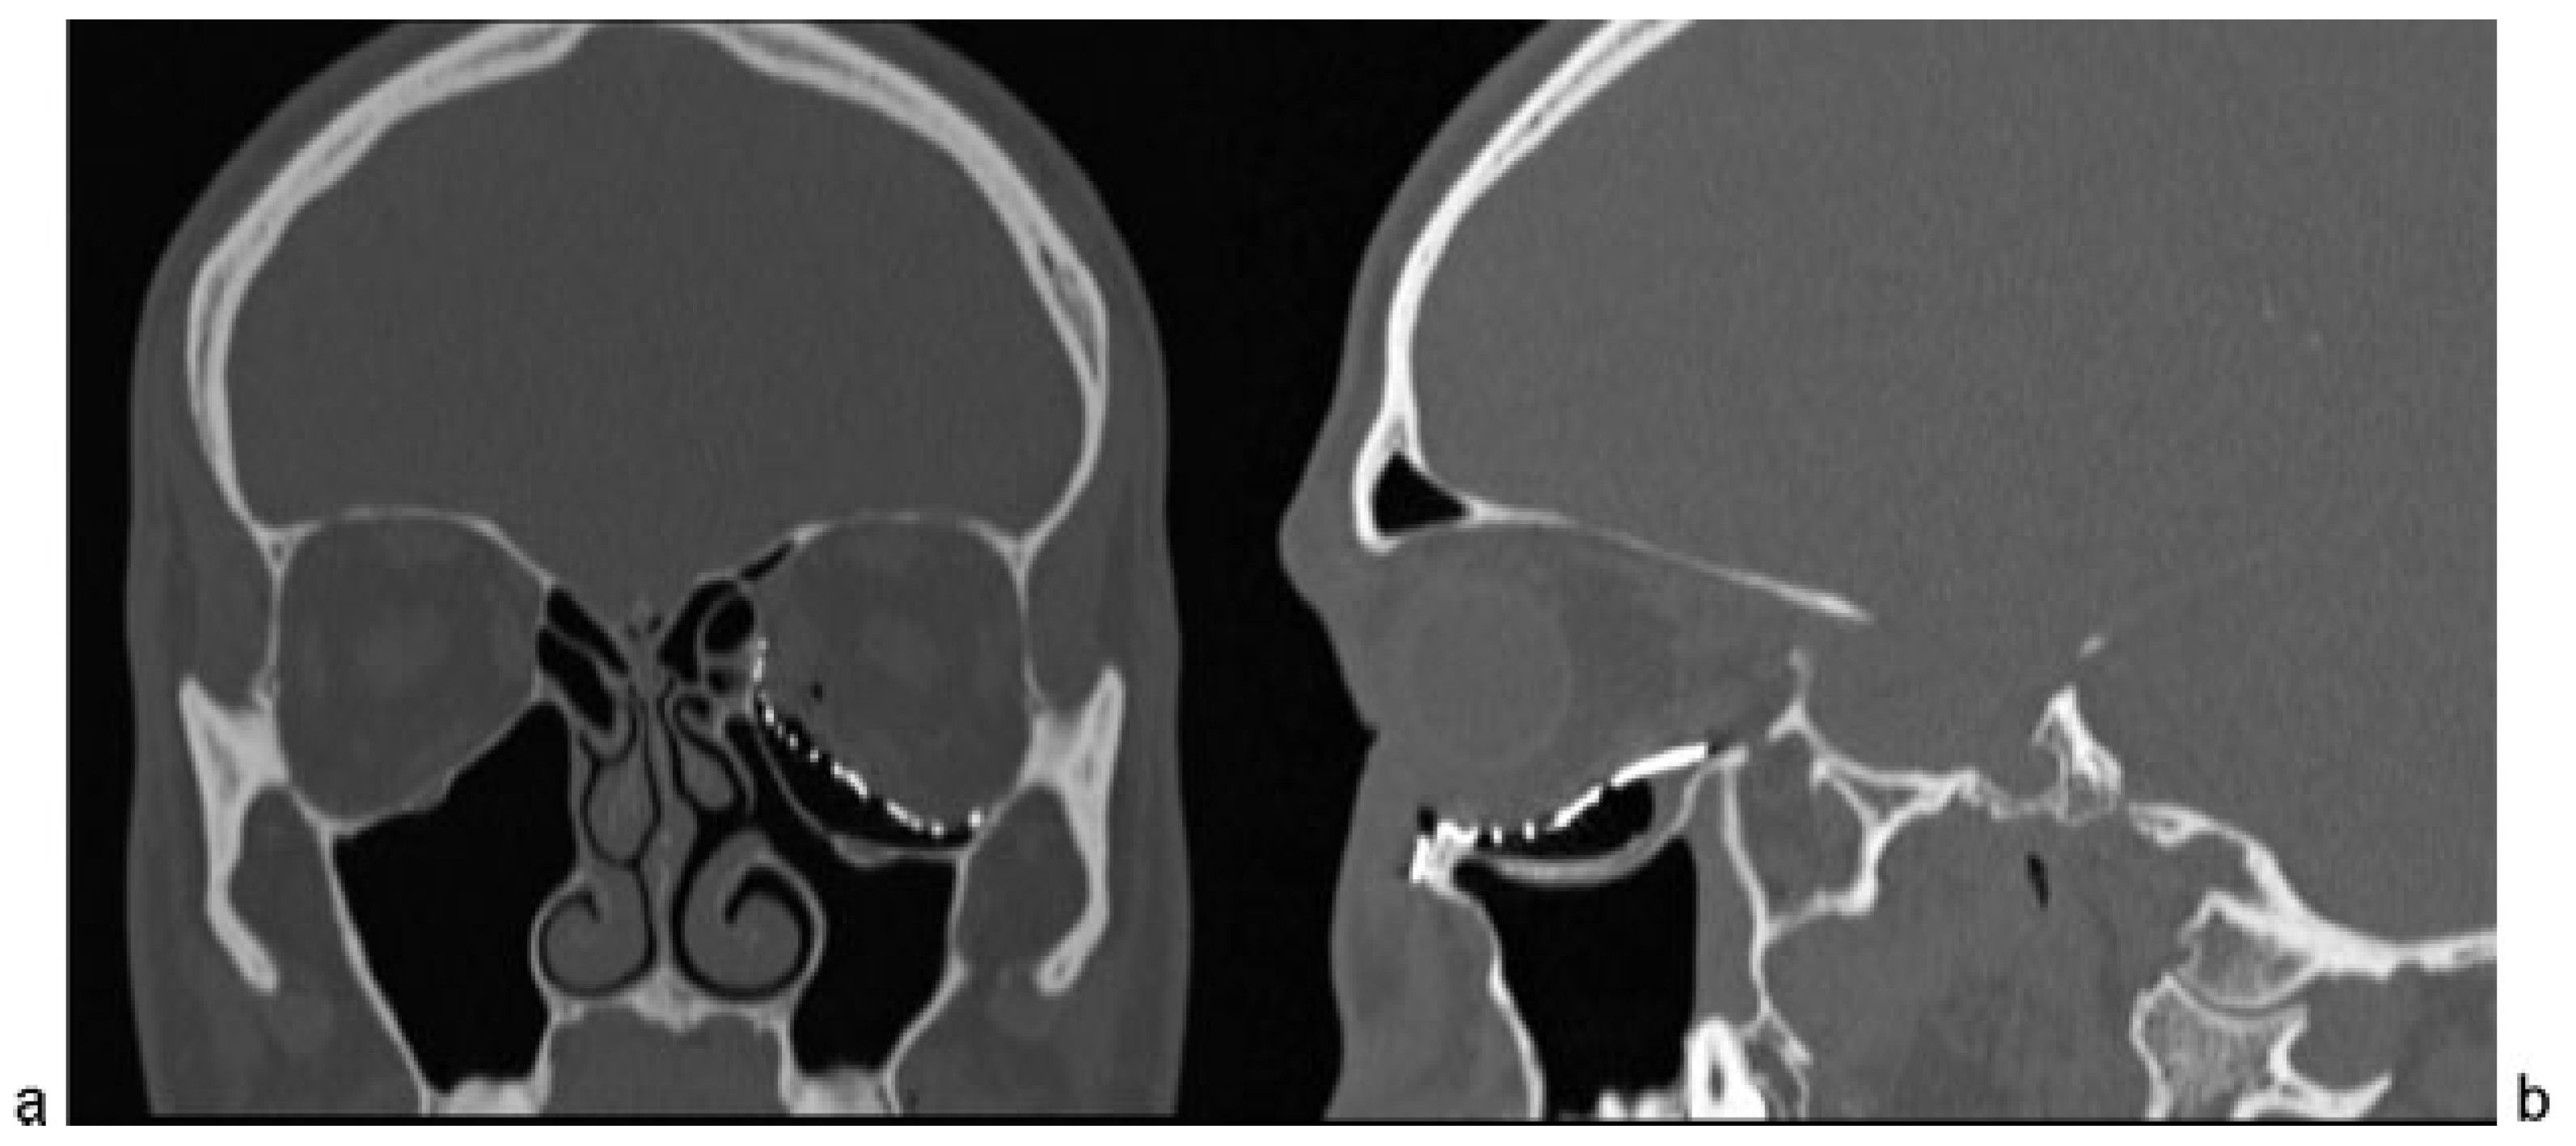

Case Report

- Remodeling and depression of the orbital floor in coronal CT scans.